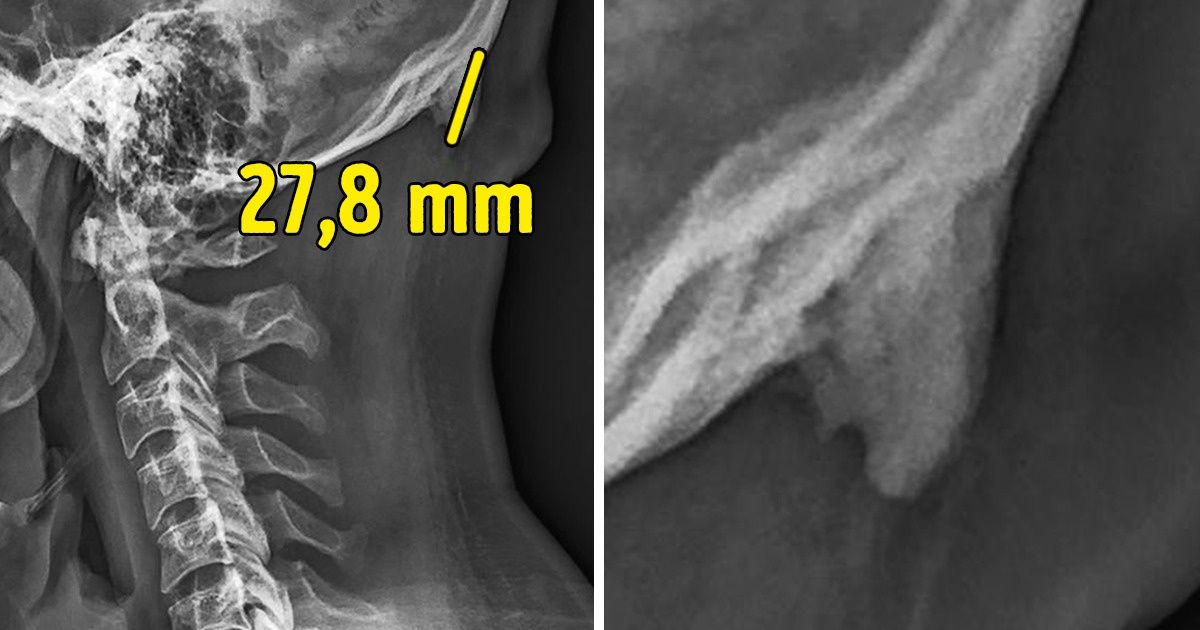

Estos científicos desarrollaron un estudio en el que les realizaron radiografías de la cabeza y el cuello a unas 1 200 personas entre las edades de 18 y 86 años. Las imágenes demostraron que al menos 1 de cada 3 participantes, jóvenes, en su mayoría, presentaba aquel hueso en forma de cuerno en la parte baja del cráneo. Se le denominó “protuberancia occipital externa”, y en ocasiones era tan grande que podía llegar a medir más de 3 cm de largo, siendo posible verlo y sentirlo a través de la piel.

El Dr. Shahar cree que los pequeños cuernos pueden ser obra de la mala postura que tienen las generaciones más jóvenes por el uso del móvil, lo que los obliga a bajar la cabeza. Mantener esta posición por largos períodos regularmente ejerce una presión en la zona que conecta los músculos del cuello con el cráneo. El peso extra que se tiene que cargar es de 4,5 kilos, lo que pesa aproximadamente la cabeza de una persona adulta, por lo que el cuerpo ha desarrollado un nuevo hueso para distribuir mejor la carga.